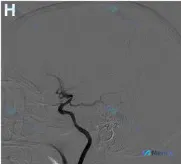

影像表现(侧位、早期动脉期):

- 颈内动脉(ICA)远端、大脑中动脉(MCA)及大脑前动脉(ACA)近端中度狭窄

- 可见豆纹动脉侧支循环(lenticulostriate collateralization)形成

第一眼看到“血管狭窄/中断”,可能容易往“急性大血管闭塞”走,但“豆纹动脉侧支”这个点,似乎在提示另一条时间线。